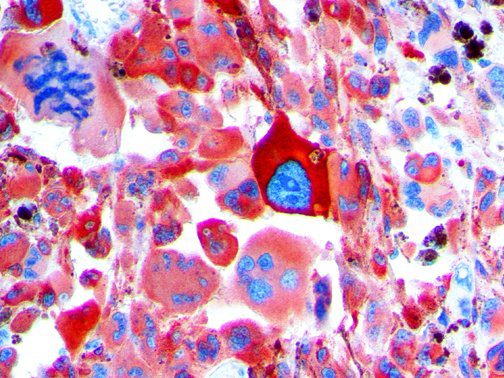

The first cytokines released are interleukin 1β (IL-1β) and tumor necrosis factor-α (TNF-α), which attract a variety of circulating white blood cells (WBCs) to the infection site, including neutrophils, monocytes, macrophages, and natural killer (NK) cells. This response, along with the antipathogenic chemicals released by these cells (i.e., complement), comprise the innate immune response. These cells directly attack the invading pathogen and also release additional cytokines, chief among them interleukin-1 and 6 (IL-6). IL-6 is essential for invoking the adaptive immune response, which calls T-cells, B-cells, and T helper (Th) cells to the infection site. IL-6 also stimulates further recruitment, proliferation and activation of macrophages.

It is the ICU physician who is most likely to witness one of the deadliest manifestations of the abnormal immunological response, the cytokine storm syndrome (CSS). This response is also referred to by some as the cytokine release syndrome (CRS). CSS is characterized by continuous activation and expansion of macrophage and lymphocyte populations, which secrete large amounts of cytokines, causing the cytokine storm. This massive cytokine release is akin to hemophagocytic lymphohistiocytosis (HLH) disease, a syndrome characterized by initial unchecked and persistent activation of cytotoxic T lymphocytes and NK cells.

This activation induces inflammatory monocytes to highly express IL-6, starting a localized and then systemic cascade effect that results in hyperproduction of IL-6, which accelerates the inflammatory process. Because IL-6 also increases vascular permeability, excessive levels cause blood vessels to become very leaky. This, along with clotting factors released from vascular endothelial cells, stimulates the coagulation cascade, resulting in microthrombosis (tiny clots), which leads to ischemia and tissue death of the kidney, intestines, heart, liver, brain and extremities.